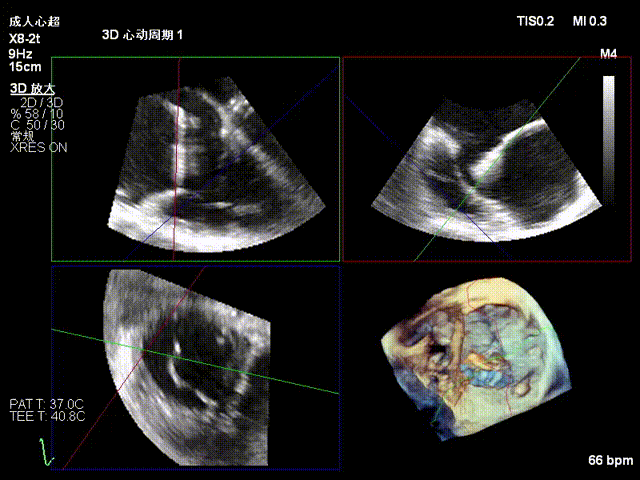

2.Annuloplasty Effect: Annular morphology remodeled, central gap significantly reduced.

Preoperative 3D

Postoperative 3D